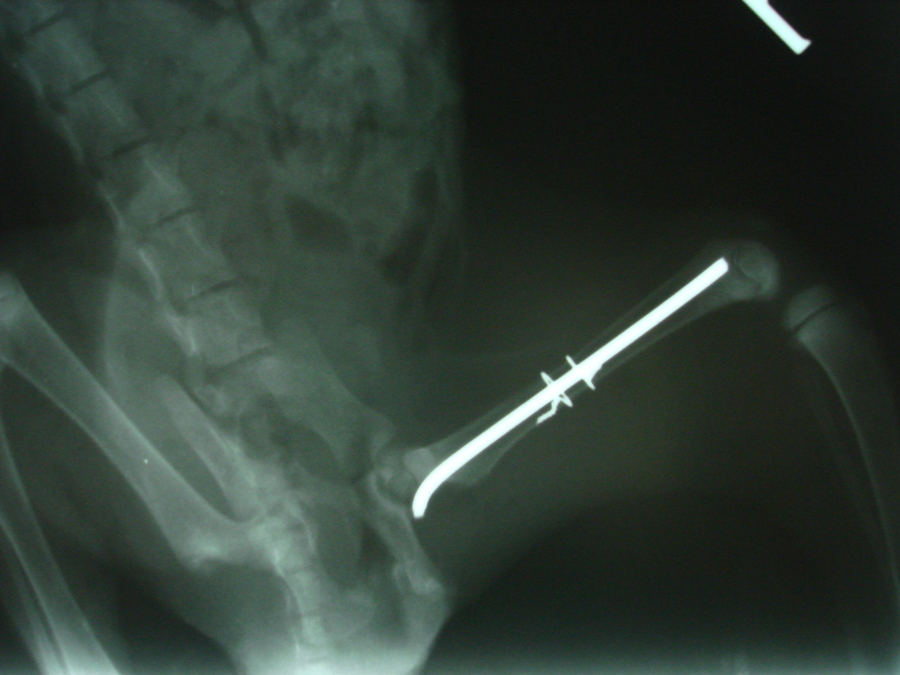

Vzhledem k tomu, že se jednalo o kompletní šikmou dislokovanou zlomeninu stehenní kosti, bylo po stabilizaci kotěte přikročeno k chirurgickému řešení zlomeniny. To spočívalo v anatomické repozici fragmentů stehenní kosti a k jejich fixaci pomoci nitrodřeňového hřebu a dvou cerkláží tenkým chirurgickým drátem zajišťující stabilitu fragmentů po operaci.

Fraktura stehenní kosti kotěte po operaci2

Fraktura stehenní kosti kotěte po operaci1